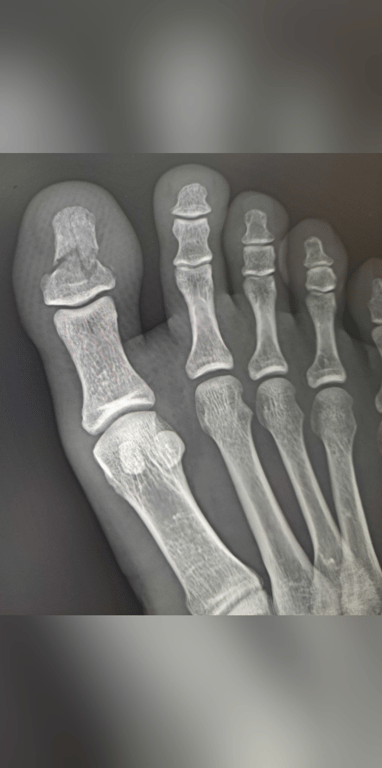

早上8點被壓斷 扛著打石機到屋頂繼續打地板 ㄍㄧㄥ到下班 才看診

就問 厲不厲害!?

(妳妹的 超級痛……)